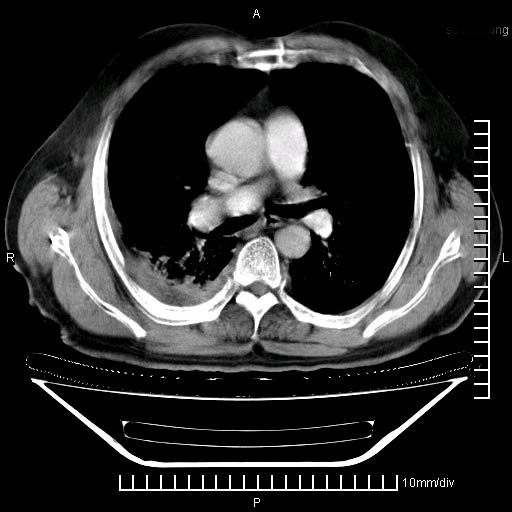

既往肺结核,近10几天,咳嗽,咳痰,右侧胸痛,疼痛较明显,右上肺斑块考虑结核灶胸膜粘连,增强,可惜动脉期没有定好,未见强化,可延迟4分后又见较明显强化,中心见低密度影,如果说结核是边缘强化,可这个灶强化的面积挺大的,让人很挠头。

强化的组织可能是膨胀不全的肺组织或炎性肉芽组织。

1)两肺继发性肺结核。2)右侧胸膜增厚+少量胸腔积液。